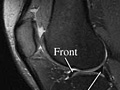

Magnetic resonance imaging (MRI) is a test done with a large machine that uses a magnetic field and pulses of radio wave energy to make pictures of the knee. Muscles, ligaments, cartilage, and other joint structures are often best seen with an MRI. In many cases MRI gives information about structures in the body that cannot be seen as well with an X-ray, ultrasound, or CT scan.

For an MRI test, you are placed inside the machine so that your knee is inside the strong magnetic field. MRI can find changes in the structure of organs or other tissues. It also can find tissue damage or disease, such as infection or a tumour. Pictures from an MRI scan are digital images that can be saved and stored on a computer for further study. The images also can be reviewed remotely, such as in a clinic or an operating room. Photographs or films of selected pictures can also be made.